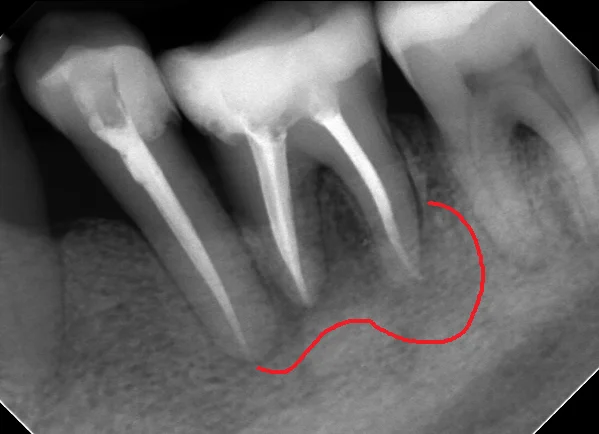

で、いつも通り、隔壁を作り・・・1回神経の治療を行った所、どちらの歯も叩いた時の症状が消えた為、神経の治療を完了させました。その際のレントゲンがこちらです。

骨が溶かされた部分はこういう感じで黒く見えてくるんですが・・・

基本的に数年単位で骨が溶かされてくるので、骨が出来るのも数年単位になってきます。

骨代謝の激しい若年者であれば1月や2月で大きく変わってくることはありますが、通常は半年くらい経過してみないことには本当に治療が上手くいったかどうかは分かりません。

今回は治療開始から治療完了までが1ヵ月半という短い期間だったにも関わらず比較的骨が出来てきているのが分かりますね。